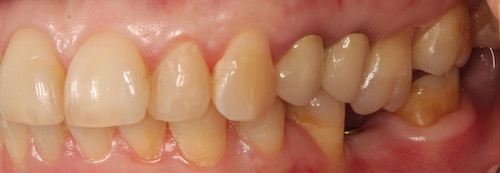

В случае большого и особенно глубокого разрушения зуба под десну, спасение последнего тоже становится под вопросом. Такие разрушения случаются в случае несвоевременного покрытия зуба коронкой. Тонкие стенки зуба не выдерживают жевательную нагрузку и просто откалываются.

Рис.3 Скол стенки зуба